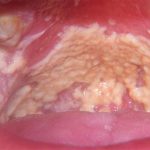

Чаще всего кандидоз ротовой полости (фото внизу) все же обволакивает всю полость творожистым налетом. Легко снимаемый в начале, он оставляет кровоточивые язвочки в запущенной форме. Кандидоз может мгновенно проявиться при ослаблении иммунитета. Довольно часто молочница у девушек появляется после злоупотребления диетами. Ослабленный организм поражает болезнь.

Атрофический процесс, который вызывает кандидоз языка (см. фото 3), сопровождается жжением, сухостью. Возникающая боль делает подвижность языка ограниченной. Язык во рту становится темно-красным. Сосочки при этом сглаживаются, становятся блестящими. Отмечается отечность, наличие пленок. Кандидоз на языке может проявляться бляшками белого цвета разнообразного размера. Снять их достаточно тяжело.

Грибок во рту покрывает спинку языка узелковыми образованиями. Довольно часто атрофический кандидоз ротоглотки располагает налет только глубоко в складках. Совсем иначе выглядит молочница во рту у ребенка до года. При этом наблюдается обильный налет творожной консистенции.